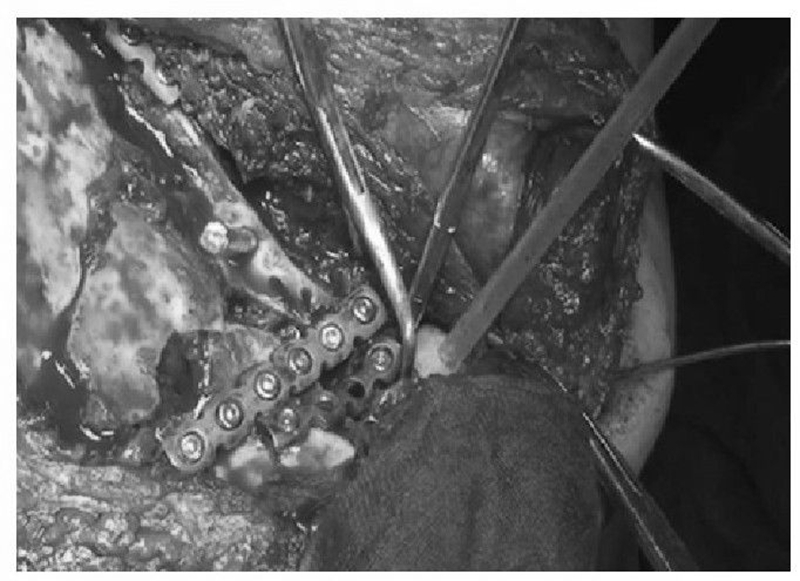

术前设计采用跨骨折区域钢板螺钉固定(图13)。术中可见纵向骨折区域骨质薄弱,骨折粉碎严重,钢板放置位置有限,操作极其困难(图14)。术中采用多块接骨板跨骨折区域固定,术后X线片及三维CT重建显示复位满意(图15)。针对此病例,如果采用缝线辅助固定技术,可使手术操作过程简化,达到同样的固定效果(图16)。

图14 术中示肩胛骨板钉固定